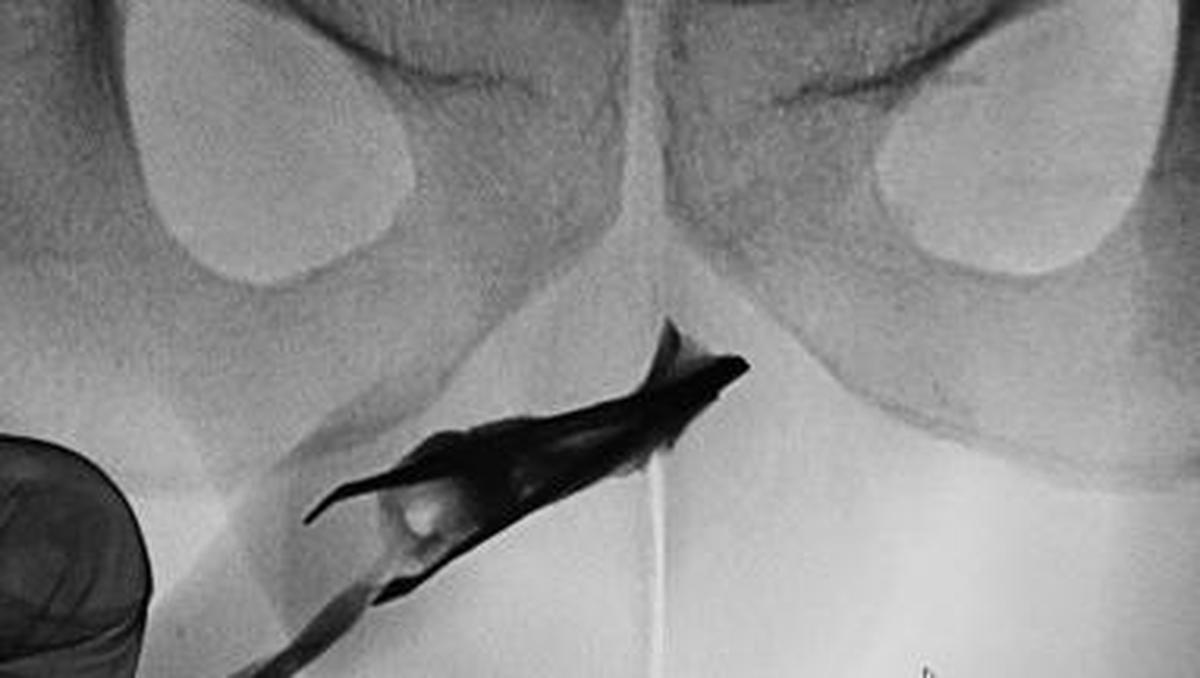

Jakarta – Seorang pasien pria berusia 22 tahun Di Arab Saudi datang Hingga Ahli Kemakmuran Didalam pinset yang menyangkut Di penisnya. Benda itu ternyata sudah ada Di 4 tahun.

Artikel ini disadur –> Detik.com Indonesia Berita News: Ngilu! Momen Ahli Kemakmuran Temukan Pinset ‘Nyangkut’ Di Mr P Di 4 Tahun